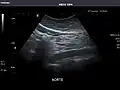

Aorta: Visualized portions normal in caliber, 16 x 15 mm.

Aorta -